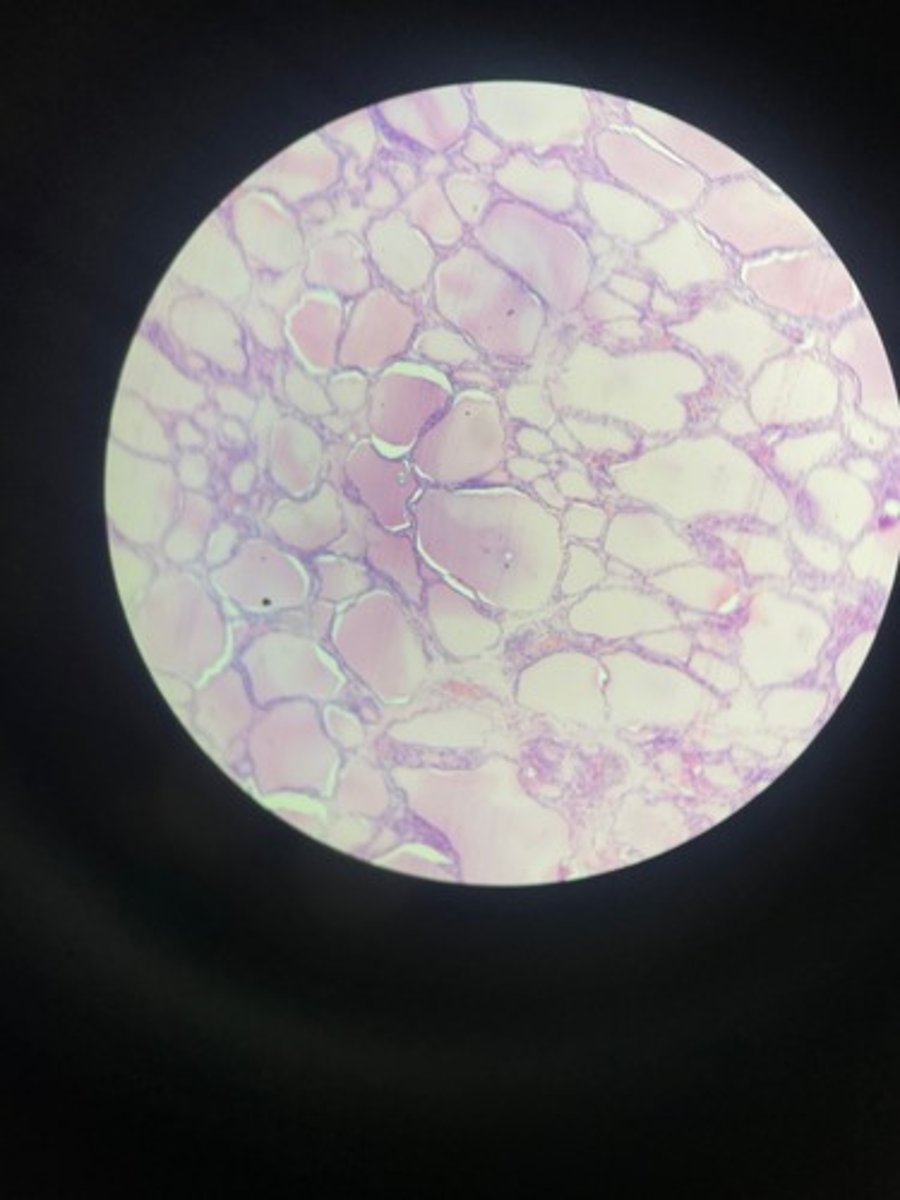

Kidney HE

Kidney HE

Kidney HE

Kidney HE

Kidney HE